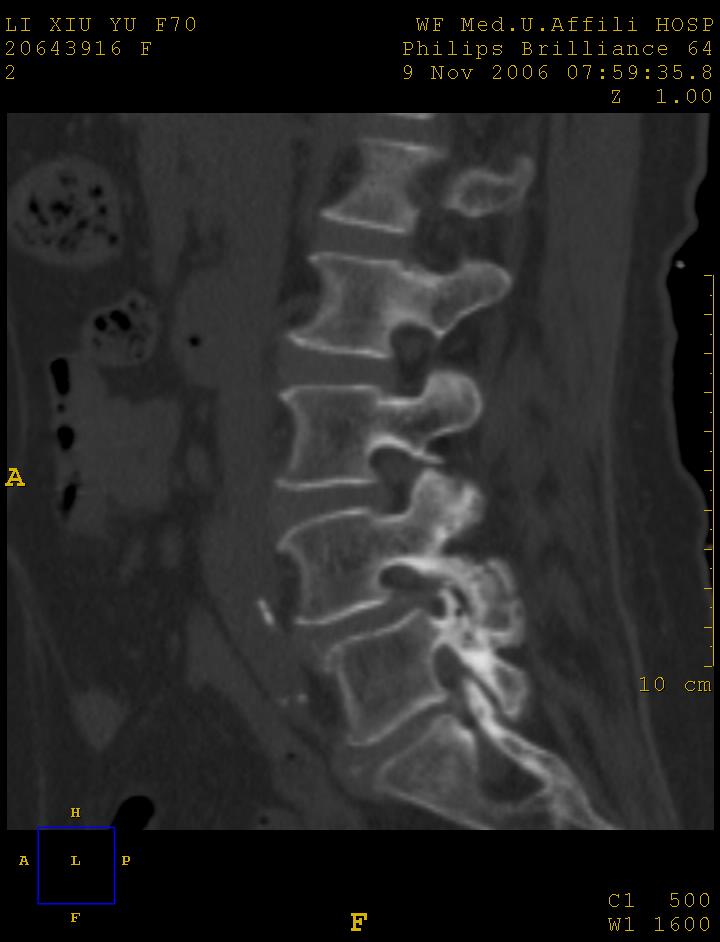

标题: CT5427:女,70岁,腰痛,清晰明了 [打印本页]

女,70岁,腰痛

l4椎体向前滑脱,椎弓裂

l3/4,l4/5,l5/s1椎间盘病变,l4以上向前ι度滑脱并椎小关节交锁、椎弓峡部断裂,椎小关节变性.

1:l4向前滑脱,l4-5小关节退性变。没有峡部裂。

1腰椎骨质增生,2l4向前滑脱(假性,矢状位椎弓峡部连续),3腰5-骶一椎间盘退变,4小关节面综合征

1 腰4椎弓崩裂,腰4椎体向前ι度滑脱并椎小关节交锁,腰4/5小关节明显增生硬化,间隙内可见真空征。

2 腰椎间盘不同程度膨出,腰4/5、腰5/骶1椎间盘突出,腰4/5椎间隙变窄,腰5/骶1间盘变性(间隙内可见真空征)。

3 诸椎体缘不同程度骨质增生,腰5、骶1后骨刺明显,腰5椎体后上缘可能有软骨结节(由于没有平扫,不易确定)。

诊断:腰椎退行性骨关节病。